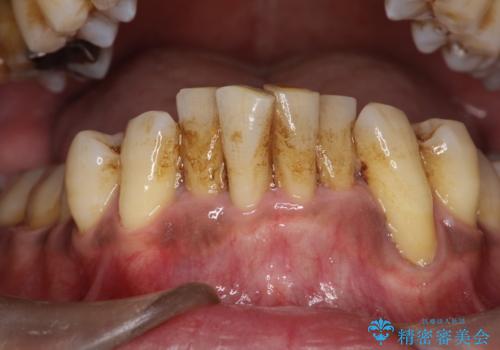

黒々とした厚みのある歯石が歯の表面に沢山付いていました。

まず、歯石除去を5回に分けて歯茎の下に付いている歯石をとりながら(麻酔あり)ホームケアの大切さ

ブラッシング指導を行っていきました。